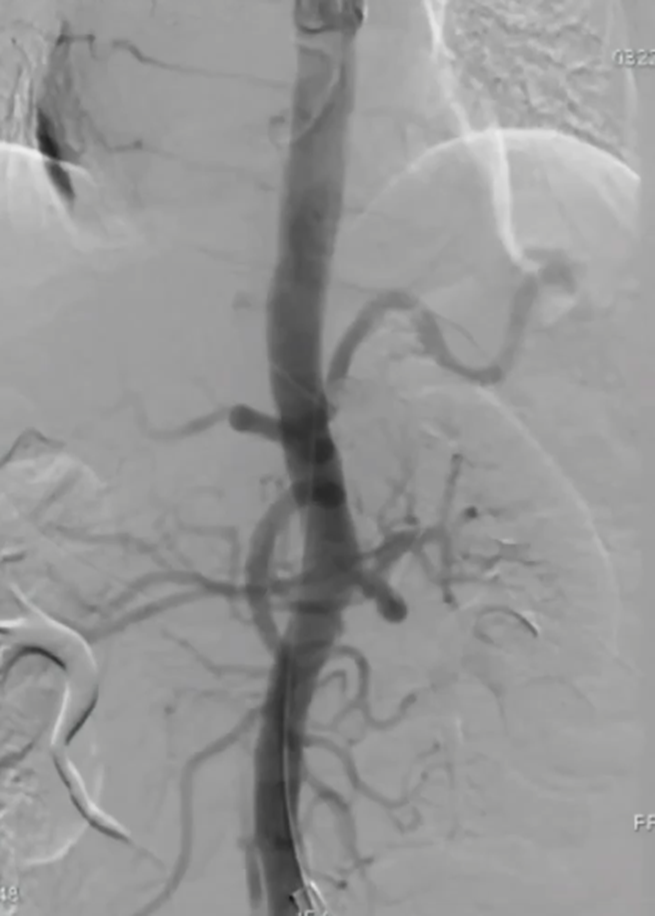

手术过程(一):术中造影证实为A型主动脉夹层,破口靠近升主动脉累及弓上分支动脉。行颈动脉转流,保持脑灌注。远端植入先健覆膜支架。

波科支架怎么样陆信武:激光原位开窗重建弓上分支治疗A型主动脉夹层_https://www.jmylbn.com_新闻资讯_第4张